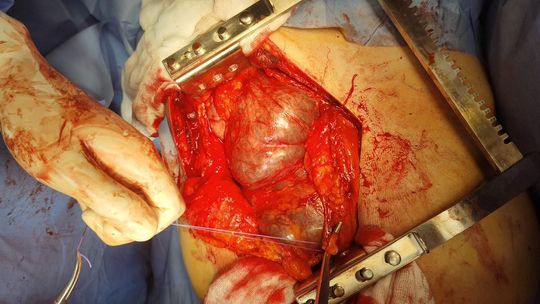

Pierwszy z pacjentów, to blisko 70-letni mężczyzna. Od lat walczył z otyłością, lecz mimo wielu prób nie udawało mu się jej pokonać. Zgłosił się do lekarza i dopiero w pogłębionej diagnostyce przeprowadzonej w kozielskiej lecznicy wykryto rozległą patologiczną zmianę w obrębie nerki. Guz utrudniał już znacznie normalne funkcjonowanie spychając pozostałe narządy w jamie brzusznej. Podjęto decyzję o natychmiastowej operacji metodą nie laparoskopową, a klasyczną, z uwagi na objętość i charakter umiejscowienia zmiany. Po 2,5-godzinnej operacji usunięto zmianę, której dokładne badania przeprowadzają obecnie histopatolodzy. Lekarze wstępnie określili zmianę jako wodonerczowo-guzowatą. Warto dodać, że objętość tego ogromnego guza to ok. 13 litrów, przy poprawnej objętości nerki ok. 300~500 ml. Zabieg zakończył się sukcesem, a pacjent czuje się bardzo dobrze i obecnie nie wymaga już leków przeciwbólowych.

Drugi przypadek dotyczy pacjentki, która miała guza umiejscowionego w bardzo trudno operowalnym miejscu. Guz był wciśnięty pomiędzy żyłę i tętnicę nerkową, dwie najważniejsze arterie odżywcze dla nerki, przy samej jej strukturze. Istniała konieczność preparowania milimetr po milimetrze, na małej przestrzeni, z zachowaniem bardzo dużej ostrożności, z uwagi na bliskość głównych naczyń krwionośnych. Guz w całości usunięto pozostawiając nerkę w nienaruszonym stanie. Zabieg wykonano w technice klasycznej otwartej, z uwagi na wielkość guza. Pacjentka czuje się dobrze.